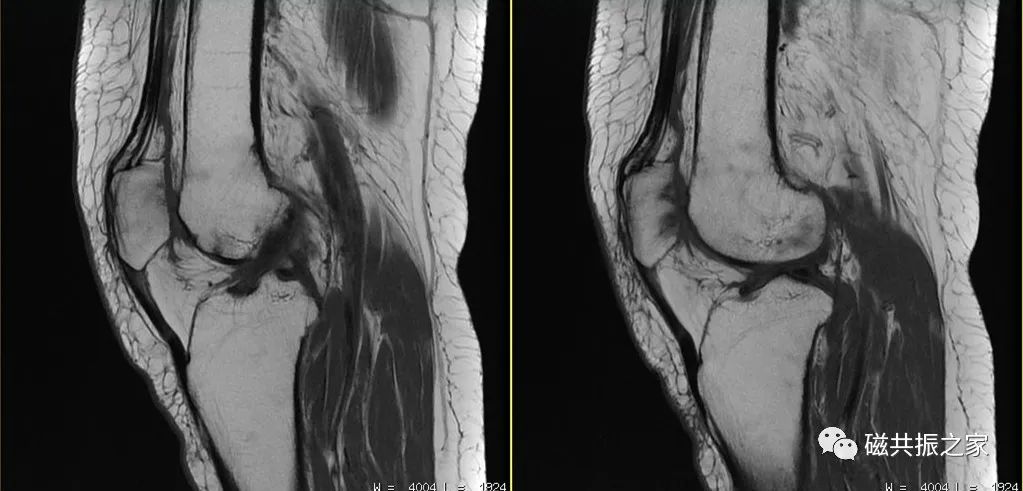

部分专用线圈其软垫会设计呈相应的屈曲角度,而大部分线圈的软垫未设计呈相应的曲度,对于这样的线圈则需要自行使用软垫使其膝关节屈曲呈临床需要的角度。

自行使用软垫使其膝关节呈屈曲状态时,应使用沙袋或软垫填充于线圈与组织间的间隙,以改善图像的均匀性。上图△,未使用填充物填充于线圈与组织间的间隙,从而获得的图像均匀度较差。

在膝关节的扫描中,合理使用沙袋不但可以改善图像质量,还可以有效的制动。